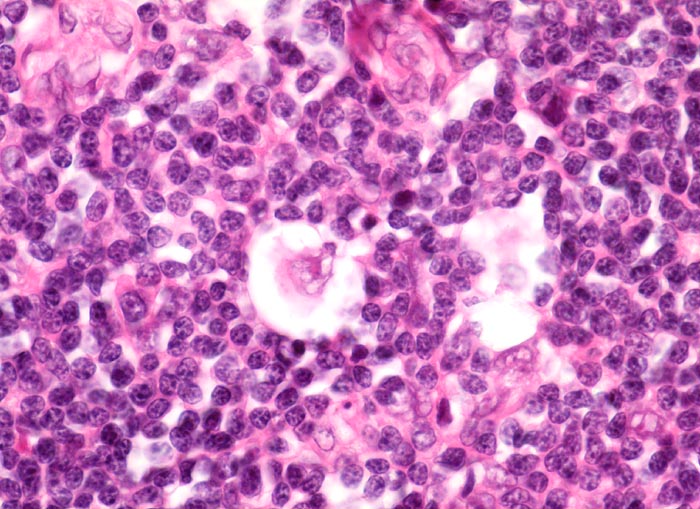

Hodgkin-Lymphom, noduläre Sklerose: Lakunarzelle

In der Bildmitte eine einkernige Hodgkinzelle mit prominentem Nukleolus. Die Zelle ist umgeben von einem Retraktionsartefakt (Lakunarzelle).

Im formalinfixierten Gewebe zeigen die neoplastischen Zellen bei der nodulären Sklerose eine Retraktion der Zytoplasmamembran. Dadurch scheint die Zelle in einer Lakune zu liegen. Deshalb werden die Tumorzellen auch Lakunarzellen genannt. Die Lakunarzellen können Aggregate bilden. Für sehr prominente Aggregate von Lakunarzellen wird der Begriff "syncytiale Variante" verwendet.